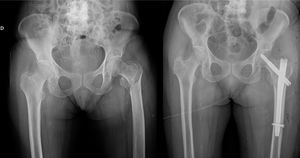

Inasmuch as the type of hip fracture is concerned, the distribution of intracapsular fractures among the people in the FCMS group relative to the group of cases of isolated hip fracture was 28.6% vs. 39.8%, while extracapsular fractures displayed a distribution of 71.4% vs. 60.2%, respectively (Fig. 1; Table 2).

The hip fractures were classified as intra- or extracapsular fractures; in addition, the management of the hip fracture and the associated upper limb fracture was documented as conservative or surgical. All the subjects who had suffered an extracapsular fracture were treated with endomedullary nailing, while those with intracapsular fractures were treated according to the Garden I or II classification with conservative treatment or osteosynthesis using cannulated screws; Garden types III or IV fractures were surgically treated with hip arthroplasty.

Of the subjects with FCMS, 8.1% (5/63) underwent surgery to treat their upper limb fracture, while 91.9% (58/63) were managed conservatively (Fig. 2).

The vast majority of the FCMS from our series were treated conservatively (91.9%) and had a negative impact on patient mortality and length of hospital stay, in line with other publications4,6,13,16–21; nevertheless, Buecking et al. treated FCMS surgically in a larger percentage of their subjects (56%) and their series reflected no increase in duration of hospitalisation (14 vs. 14 days, p=0.799) or mortality rate (9.5% vs. 5.9%, p=.003) in their cases of FCMS.17 Lee et al. observed no significant differences in mortality or hospital stay in people with concomitant upper extremity fractures of either the distal radius or proximal humerus, albeit they did observe better functional outcomes among individuals who suffered an associated fracture of the distal radius as opposed to the proximal humerus.22 Ganta et al. compared cases of concomitant proximal humerus fractures that underwent conservative vs. surgical treatment, and found no significant differences with respect to length of hospitalisation or destination at discharge. They indicate that a greater proportion of patients return to their former functional status; however, this difference has not reached the level of statistical significance (70% vs. 52%, p=.342).23 Therefore, one should contemplate the possibility that patients with a hip fracture and FCMS might benefit from surgical treatment of the upper limb injury, despite the fact that in other circumstances, this fracture would warrant conservative treatment.